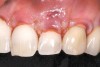

A 54-year-old non-smoking woman presented for correction of deep-wide gingival recession in the maxillary anterior (Figure 1 through Figure 3). The patient’s desires were to correct the gingival recession, balance the heights of contour of the tissues, and possibly undergo esthetic enhancement of the maxillary anterior with veneer restorations.

Figure 1  Case One Pretreatment clinical view, Case 1, maxillary right.

Figure 1

Figure 2  Case One Pretreatment clinical view, Case 1, maxillary anterior.

Figure 2